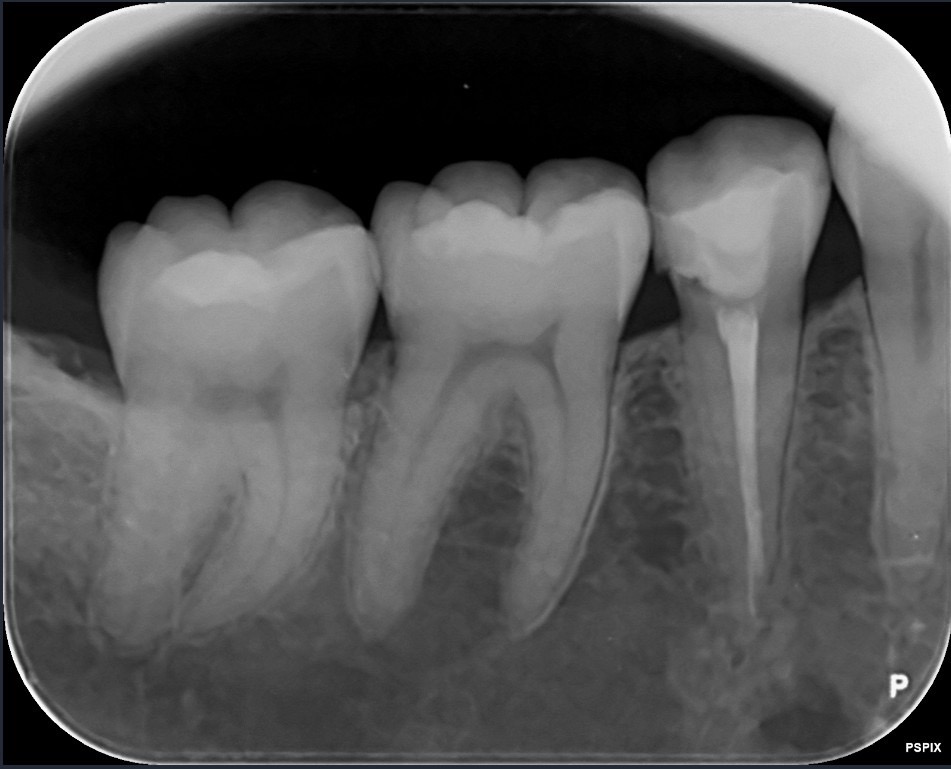

Periapical X-Ray (PA)

เพื่อดูฟันซี่ใดซี่หนึ่งโดยเฉพาะ ที่ คอร์ เนอร์ คลินิก ทันตกรรม จะไช้ประกอบการรักษาราก และอุดฟัน เป็นหลัก

Bitewing X-Ray (BW)

เพื่อดูด้านประชิดของฟัน